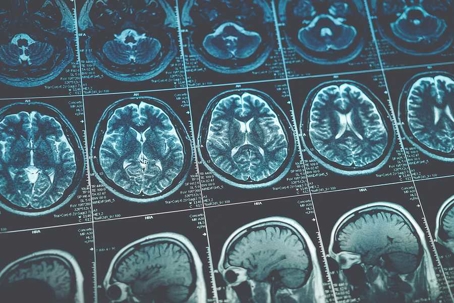

A mild TBI victim may visit a doctor right away if they know they hit their head or are starting to experience unpleasant symptoms. Sometimes, victims do not realize they’ve suffered a brain injury so they wait several days to see a doctor. Either way, the doctor can diagnose this injury based on your symptoms and ability to perform certain reflex and coordination tests. The doctor must rely on these tests to diagnose a mild TBI because this type of injury is not visible on MRI and CT scans.

People who have sustained severe TBIs are usually brought to the emergency room via ambulance. Severe TBI victims are unconscious when they are first seen by a doctor, so there’s no way to discuss the patient’s symptoms. But, doctors should be able to tell the patient has a head injury based on their observations alone. Doctors often perform imaging tests to determine the extent of the brain damage. Since a severe TBI causes structural damage to the brain, these injuries will appear on CT or MRI scans.